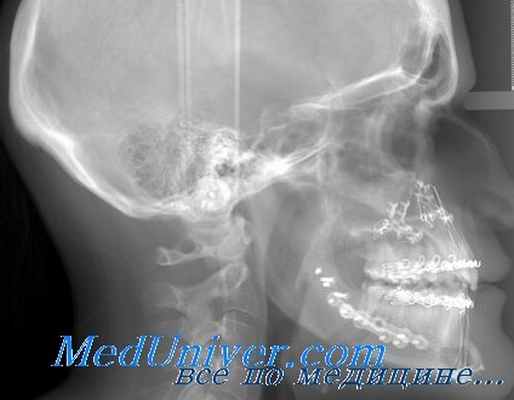

1 Рентгенография черепа - прицельно-боковая. проекция - производилась при следующих физико-технических условиях: 57-56 кВ. 150 мА, экспозиция 1,65 с, кожно-фокусное расстояние 1 м. Боковые рентгенограммы проводили в положении половы больного как на левой, так и на правой стороне, что позволяло выявлять малейшие неровности и асимметричные деструкции стенок турецкого седла, обусловленные неравномерным ростом аденомы. Томографию также выполняли в правой и левой боковых проекциях с шагом 3 мм при угле качания трубки 70°. При анализе рентгенограмм определяли размеры турецкого седла, его форму, обращали внимание на структуру стенок. При этом мы исходили из представления о том, что турецкое седло у больных с микроаденомами гипофиза может иметь нормальные размеры, при небольших аденомах его величина находится на верхней границе нормы или несколько превышает ее. Наш опыт свидетельствует о том. что такие общеизвестные симптомы опухолей гипофиза, как двухконтурность дна. расширение входа в седло, наблюдаются не часто. Поэтому мы придавали значение таким симптомам, как локальный остеопороз стенок турецкого седла, тотальный остеопороз стенок без изменения структуры костей свода черепа, локальное или тотальное истончение стенок, неровность, выбухание участка внутреннего контура стенки, частичное или тотальное истончение передних или задних клиновидных отростков. На томограммах аналогичными признаками являются локальное истончение кортикального слоя стенки или дна турецкого седла, локальный остеопороз стенок, небольшое выбухание дна. Указанные симптомы могут наблюдаться самостоятельно или в 'сочетании.

Рентгенография черепа. Вначале больному с подозрением на опухоль гипофиза следует произвести боковую и передне-заднюю рентгенографию черепа. Специалисты значительно расходятся во мнении относительно нормальных размеров, формы и тонких особенностей костной структуры турецкого седла на рентгенограммах. На обычном боковом снимке максимальные размеры передне-заднего диаметра, т. е. наибольшего расстояния от передней вогнутости турецкого седла до переднего края его спинки, не превышают 17 мм, а максимальная глубина гипофизарной ямки, т. е. наибольшее расстояние между дном и перпендикуляром, опущенным от вершины спинки седла на его бугорок, составляет 13 мм [128]. Однако определение размеров турецкого седла мало

Рис. 7—12. Методики непрорентгенологпчеекого исследования, применяемые для оценки патологии гипофиза. а — (расширенное турецкое седло с разрушенным дном и спинкой у больного с СТГ-секретирующей опухолью. Видны также увеличенные размеры синусов; б — латеральная томограмма турецкого седла, на которой видна локальная эрозия передней части дна (стрелка) у

больного с небольшой пролактинсекретирующей опухолью: в — латеральная томограмма турецкого седла, на которой видна интра- и экстраселлярная кальцификация (стрелки) у больного с краниофарингиомой; г — пневмоэнцефалограмма, на которой можно видеть воздух в турецком седле у больного с синдромом «пустого» турецкого седла Виден ободок остаточной гипофизарной ткани вдоль нижней и задней части турецкого седла- д е — нормальная и патологическая картина при двусто-

ронней ангиографии сонных артерий (стрелка), обнаруживающая верхнее и боковое смещение обеих передних мозговых артерий вследствие интенсивного супраселлярного роста опухоли гипофиза: ж — компьютерная томографическая сканограмма и з — усиленная (путем инфузии контрастного вещества) сканограмма, обнаруживающая супраселлярное распространение опухоли гипофиза (стрелки) (любезно предоставлено D. Fatal, госпиталь Michael Reese).

что дает для диагностики опухоли гипофиза [129], поскольку при превышении нормальных размеров обычно имеются другие признаки его патологии, а при явных изменениях по другим критериям размеры седла часто остаются в пределах нормы. Пытаясь точнее определить размеры турецкого седла, DuChiro и Nelson [1] для вычисления его объема предложили использовать ширину, измеряемую на переднезаднем снимке черепа. По данным этих авторов, максимальный объем седла в норме составляет 1100 мм 3 , хотя при другом способе расчета была получена цифра, почти вдвое превышающая эту [130]. Более субъективной является оценка формы турецкого седла, и для передачи впечатления о минимальном его увеличении применяют такие термины, как «набухание» или «баллоновидное» расширение. Имеются также разногласия в отношении того, являются ли вариантами нормы или ранними признаками опухолей небольшое истончение или эрозия кортикального слоя кости, формирующей твердую пластинку седла, а также двойной контур его нижней поверхности («двойное дно»), что встречается у 30% лиц без подозрения на опухоль гипофиза [131].